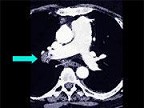

- 多项选择题该病人突发胸部疼痛,进行性呼吸困难, 行X线片检查,提示右下肺病变, 急诊CT平扫加增强,如图所示 ( )

B、SCT增强扫描示右侧肺动脉主干完全性充盈缺损

C、右肺动脉开口处见不规则软组织密度影

D、考虑为右侧肺动脉(中央性)栓塞